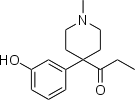

Ketobemidones

Structures